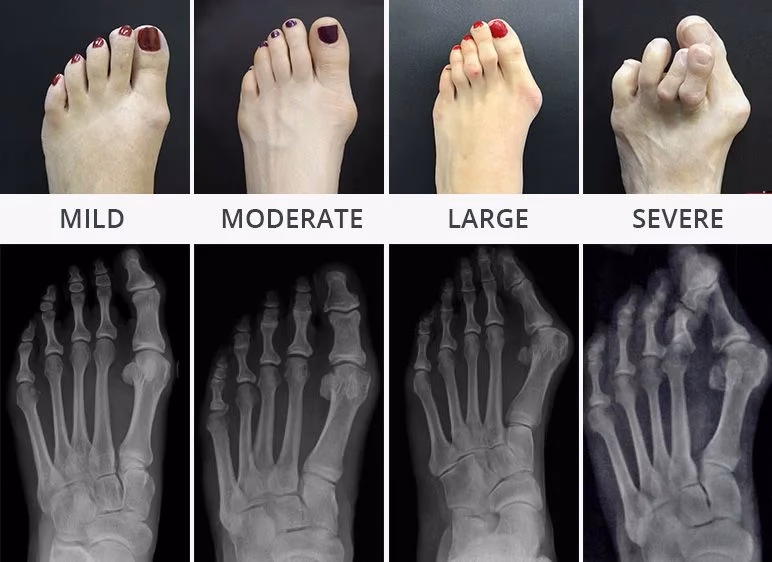

En knyst er en knogleudvækst, der dannes på siden af storetåens grundled. Den opstår, når storetåen begynder at dreje indad mod de andre tæer, hvilket får leddet til at stikke ud. Dette kan medføre, at foden bliver bredere, og at det bliver smertefuldt at gå i almindeligt fodtøj. Symptomerne omfatter smerte, hævelse, rødme, hård hud og en synlig bule ved storetåens grundled.